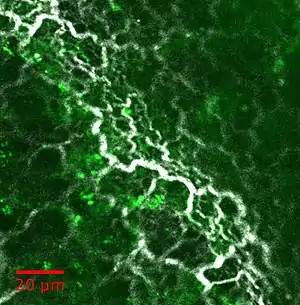

SHG microscopy and its expansions can be used to study various tissues: some example images are reported in the figure below: collagen inside the extracellular matrix remains the main application. It can be found in tendon, skin, bone, cornea, aorta, fascia, cartilage, meniscus, intervertebral disks...

Myosin can also be imaged in skeletal muscle or cardiac muscle.